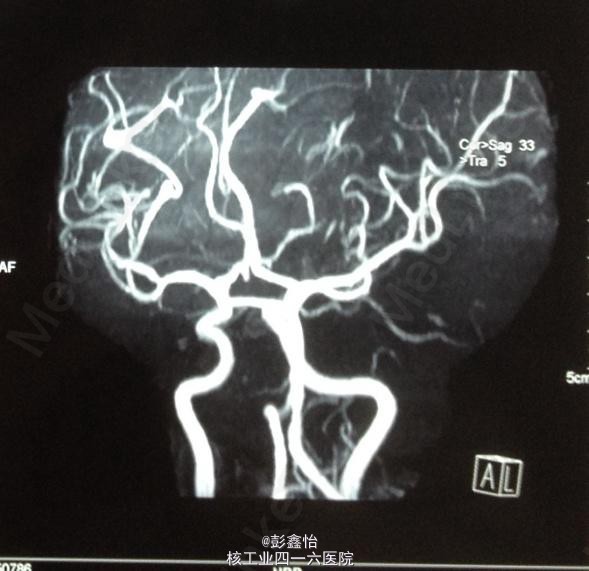

PE: NE:神经专科查体均正常; ABCD2评分为3分 NIHSS评分为0分; 入院后辅助检查均正常,CT、MRI+MRA、脑电图、视频脑电监测均未见异常。

因患者无明显肢体抽搐及局部泛化过程,脑电监测正常,基本可除外癫痫发作。诊断TIA,予以阿司匹林、他汀降脂等治疗,但TIA继续发作。 追加血管评估,但TCD、DSA、颈部血管超声均未发现异常,在原有治疗基础上,予以双抗、改善循环、营养神经加强治疗 但患者仍频繁发作TIA,3天内共发作20余次。判断为治疗抵抗,继续加用抗凝、脑保护,最后加用羟乙基淀粉扩容治疗后发作终止,但患者出现右侧肢体轻偏瘫。 复查DWI:左侧基底节区出现急性梗死灶; 复查MRA、DSA均未见异常。